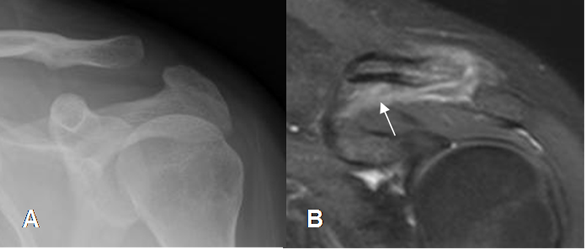

Fig 55. Esguince de articulación acromioclavicular.

A: Rx AP. Aumento patológico en el espacio acromioclavicular, por esguince.

B: RM coronal en STIR. Hiperintensidad y ausencia de los ligamentos coracoclaviculares, por esguince G III.